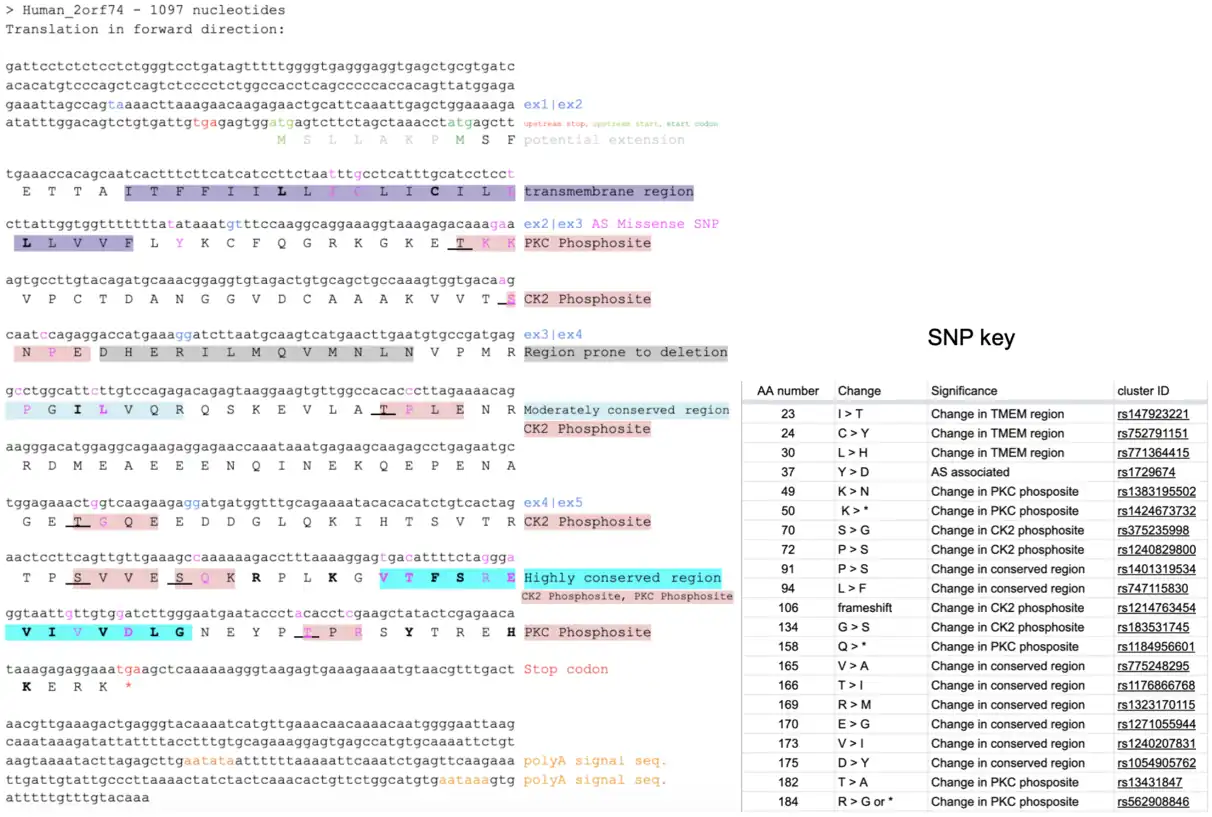

The above figure depicts a conceptual translation of isoform 1 of C2orf74 made using SixFrame.[10] Exon boundaries are depicted in blue font. The 5'UTR of this protein is shown to have an upstream in frame stop codon (red), and an upstream in frame start codon (green). The putative N-terminal extension is depicted in light gray. The N-terminal transmembrane domain is highlighted in lavender. Regions conserved among orthologs are highlighted in cyan, while regions prone to deletion are highlighted in gray. Phosphorylation sites are highlighted in red with the phosphorylated amino acid underlined. Significant SNPs are highlighted in pink with a key pictured to the right detailing the type of change and reason for inclusion. Polyadenylation signals in the 3'UTR are highlighted in orange.

Isoform 1 of the C2orf74 protein has a calculated molecular weight of approximately 21 kDa, and a pI of 5.74.[11][12] It does not display any unique amino acid composition, cysteine spacing, number of multiplets, or periodicity.[13] This protein isoform has a putative 7 aa N-terminal extension[8] It contains a 21 aa transmembrane region at position 7.[3]

Domains

The transmembrane region begins 7 amino acids from the N-terminal end of the protein, and ends at the 29th amino acid in humans. This region has been identified by NCBI,[3] as well as being supported by biochemical analysis. The biochemical qualities characterizing this region as a transmembrane region include a neutral charge cluster and a high-scoring hydrophobic segment, as well as alpha-helical secondary structure.[13][14] This region is also highly conserved among all orthologs, indicating it as a region of functional significance.[15]

The region downstream of the transmembrane region is considered a domain of unknown function (DUF) within pfam 15484.[3] Approximately 52% of this portion of the protein is considered to be disordered, making confidence in prediction of domain function difficult.[16] However, the C-terminal end is highly conserved among all orthologs.[15]

Aside from Crohn's disease, C2orf74 has also been found to be a susceptibility locus for ankylosing spondylitis,[4] and generally for other nondescript autoimmune conditions.[5] The SNP believed to play a role in C2orf74's relationship to ankylosing spondylitis is found within the coding region of the gene, and is denoted in the conceptual translation found in the Protein section above.[6]

At 36aa there is a missense SNP that may be either a Tyrosine (Tyr, Y) or an Aspartate (Asp, D). This is caused by a SNP is associated with ankylosing spondylitis can be found at 319 bp on transcript variant 1[4]